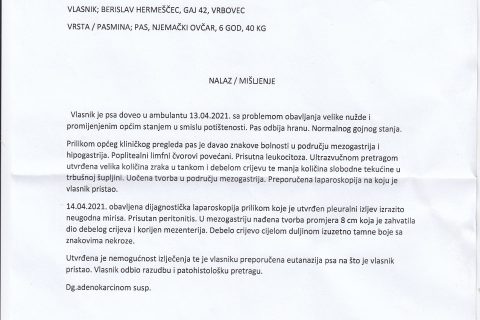

Ovdje objavljujem drugu rtg sliku, ali ne znam da li je to slika rendgena od 13. ili 14. travnja 2021. i da li je to zaista rendgen moga psa jer nema nigdje moga imena ili imena moga psa. Nakon toliko dana, taj nalaz može biti podmetnut i ne mora biti slika moga psa.